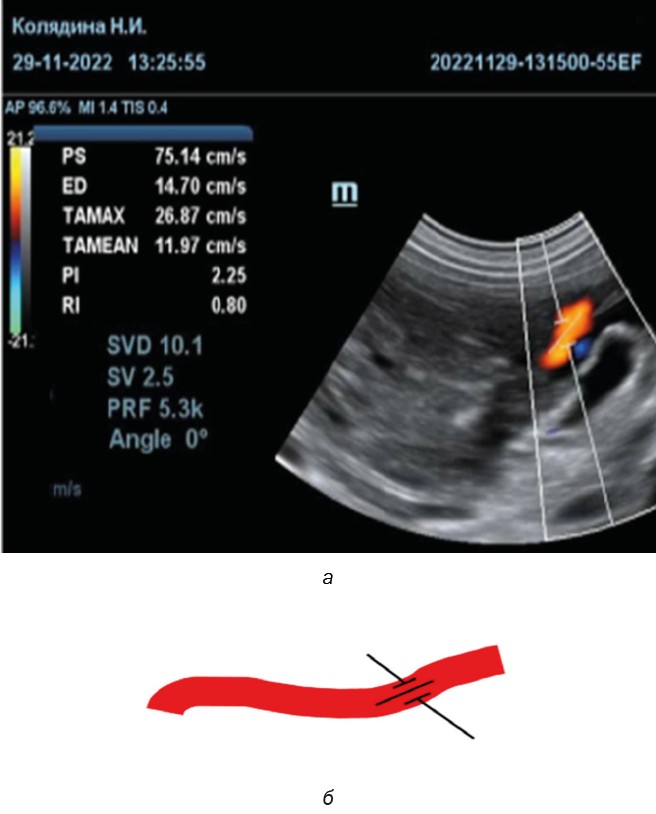

Fig. 6. The method of determining the umbilical artery resistance index (а) and a schematic drawing of the insonation angle (б)

Source: fig. 6a compiled by N.I. Kolyadina, A.V. Shumeyko on the Mindray Vetus 8 Ultrasound Machine; fig. 6b created by A.V. Shumeyko in Microsoft Paint.